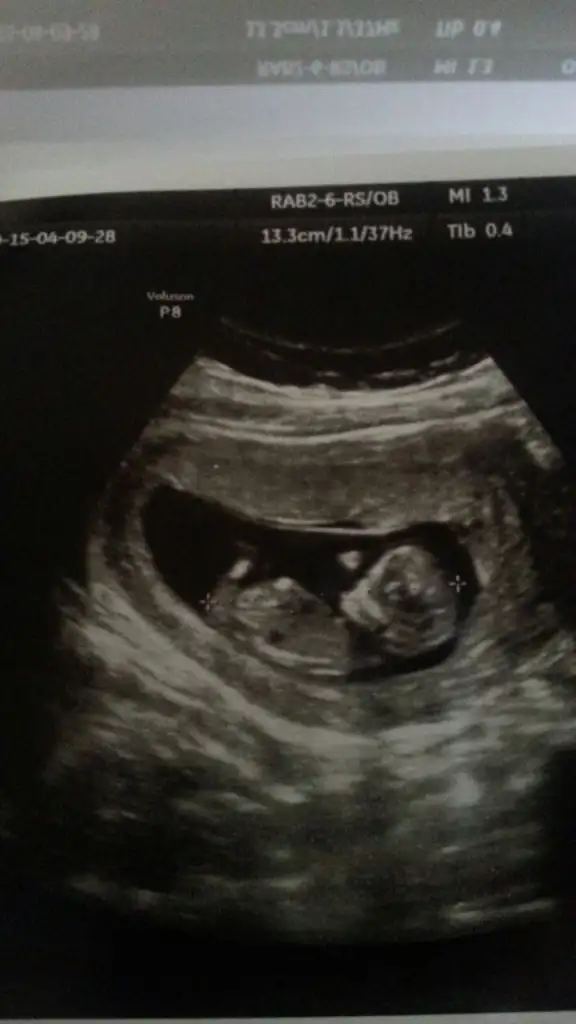

İlk fotoğrafa sanırım meleksr erkek demişti. Tam hatırlamıyorum ama kim dedi diye.. Sonra kız diyen de oldu erkek de. Daha küçük büyüsün dedik. 2. fotoya daha çok kız denilmişti. Ben pek anlamıyorum kordon paralel falan olaylarını. Nubu biliyorum biraz, onu da tam göremedim ikinci fotoda. Bir şey de hissetmiyordum cinsiyetle ilgili.. İlk olacak nasipse ama etrafımda hep kız çocukları var. Yeğenime baya yarı annelik yapmıştım falan.. Erkek çocuk hayalim hiç olmadı.. erkek annesi olmakla ilgili hiç fikrim yok :/ Şaşkınım biraz.. İnşallah sağlıkla gelsin de, öğrenirim bakalım.. %90 erkek dedi. Kesin değil mi yani dedim, kordon falan olabilir bir ihtimal dedi. Yanlış görmüş olabilir mi ki acep? Görücez 2 hafta sonra bakalım..